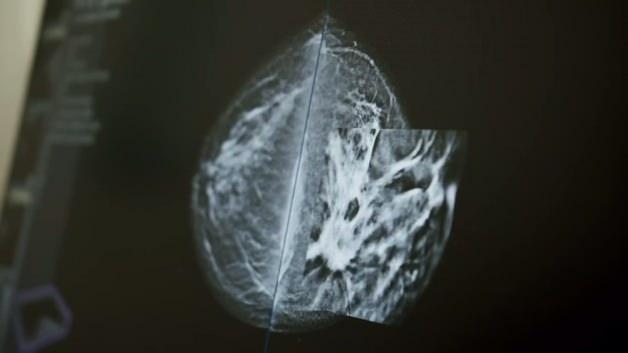

Klasik ultrason ve mamografi yöntemlerinin meme kanseri taramalarında temel araçlar olduğunu ancak ABUS teknolojisinin bu süreci önemli ölçüde geliştirdiğini vurgulayan Doç. Erok, “ABUS, memeyi otomatik ve üç boyutlu olarak tarayarak objektif görüntüler oluşturur. Klasik ultrasonda operatör kaynaklı farklılıklar olabiliyor. ABUS, bu değişkenliği ortadan kaldırarak her bölgede aynı kalitede ve detayda görüntü elde edilmesini sağlıyor. Çekim teknisyen tarafından yapılıyor, ardından görüntüler radyolog tarafından detaylı şekilde değerlendiriliyor” diye konuştu.

ABUS’un mamografinin alternatifi değil, tamamlayıcısı olduğunu vurgulayan Doç. Dr. Erok, yöntemin özellikle yoğun meme dokusuna sahip kadınlarda yüksek başarı sağladığını ifade etti. Doç. Dr. Erok,“Yoğun memelerde klasik mamografi ile bazı lezyonlar doku içinde gizlenebiliyor. ABUS bu alanları çok daha net gösteriyor. Bu da erken tanı oranlarını anlamlı şekilde yükseltiyor: ABUS çekimleri ortalama 15–20 dakika sürüyor. Meme boyutuna göre süre uzayabiliyor. Meme kanserinde en güçlü silahımız erken tanıdır. ABUS gibi yeni teknolojiler sayesinde hastalığı çok daha erken evrede saptayabiliyoruz. Bu nedenle taramalarımızı ertelememeliyiz” ifadelerini kullandı.